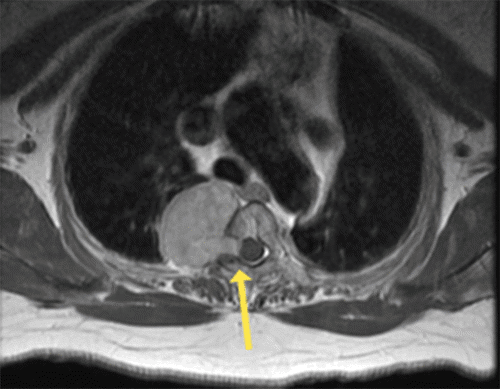

Figure 2. Repeat MRI in Routine Office Follow-Up: Sagittal FLAIR Sequence. Published with Permission

A. The mass essentially unchanged in size from the prior study, about five years prior.

B. Patient subsequently developed neurologic sequelae and was sent for repeat axial T2-weighted image, which demonstrates interval increase in the size of the mass (asterisk), which now extends into the spinal canal and causes mass effect on the cord (arrow).

The patient was followed for 30 years without progression and had a repeat MRI, which showed stability of the mass (Figure 2). Over a few months, the patient noticed difficulty walking and numbness in the torso and lower extremities. She was re-evaluated in the office, where her neurologic constellation of symptoms included vague decreased sensation below the level of T4, unsteady balance, and abnormal plantar (Babinski) reflex. No focal motor deficits were present in the lower extremities. A repeat MRI was then obtained at the time of showing an increase in the size of the mass compared to before (Figure 2), with growth inwards, causing a significant mass effect on the spinal canal and moderate to severe compression of the spinal cord. It also caused severe right neural foraminal narrowing at the level of T2–T3, resulting in nerve-root impingement (Figure 2).